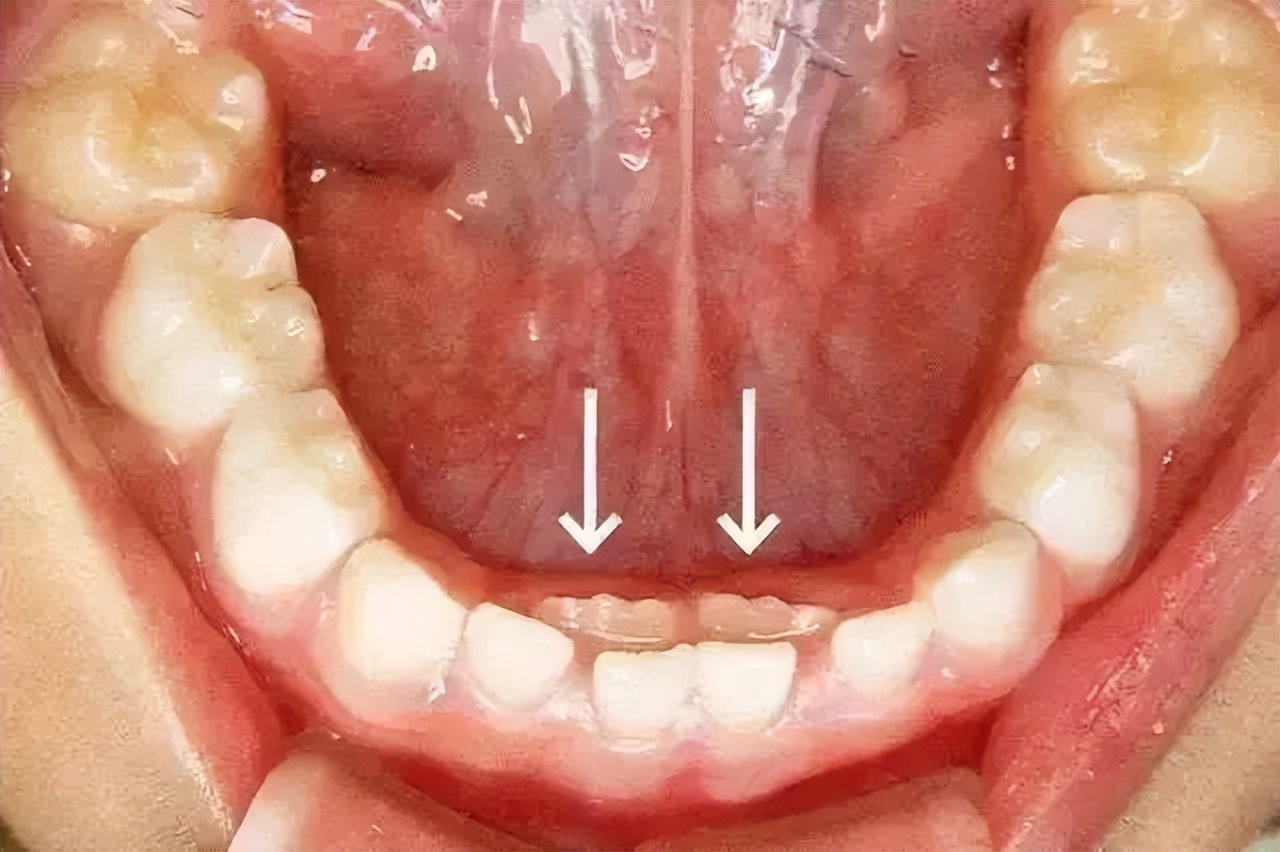

在牙齿更替的过程中,很多父母也会发现这样的情况,那就是当孩子的旧牙还未完全脱落时,新牙就已经萌出了,这时候孩子就长出了非常难看的“双排牙”。

但与此同时,她发现儿子的另外一颗牙齿也松动了,且松动的牙齿后面已经萌出了新的牙齿,两颗牙齿并排长在牙龈上,看上去非常别扭。

当孩子出现双排牙齿之后,及时拔掉乳牙并非是为了美观,而是为了给恒牙提供正常的生长空间。

如果任由两颗牙齿共存生长,久而久之,孩子则会出现恒牙畸形或生长而及时将乳牙拔出,而及时将乳牙拔出,恒牙就会渐渐归位生长。